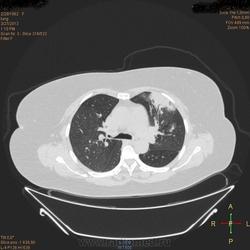

Здравствуйте, коллеги .Нужна помощь.Больная страдает Бронх.астмой.Беспокоять кашель,одышка , слабость, боль левой грудной клетке.Была температура 37,5- 38,0.Данный момент получает цефомизин темпер нормализовалось.Хочеть стационарное леч.Обратите пожалуиста на молочные железы, справа была операция год назад .Беспокоять боль правой мол.железе.

Во-первых, нет дайкомов. По представленным изображениям, изменения в левом легком дифференцировал бы между ТЭЛА мелких ветвей и организующей пневмонией, справа - пока вариантов нет (нужны дайкомы).

+1. Диф. диагностика между ОП и ТЭЛА обоих легких. Исключить ТЭЛА методом КТ с в/в боюсным контрастированием.